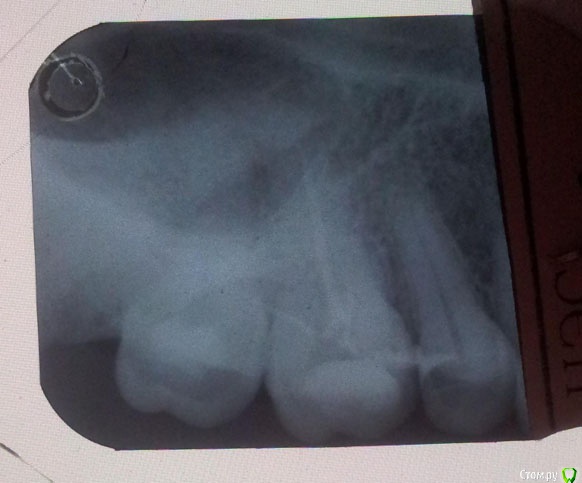

Рената74 Опубликовано 21 апреля, 2015 Поделиться Опубликовано 21 апреля, 2015 (изменено) Добрый день! Обратилась в прошлый вторник, 14.04 к врачу с чуствительностью зуба на холодное, горячее. Какой зуб реагировал я и сама не знала - просто ноющая боль была, не сильная и не долгая. Причина была обозначена врачём после снимка - пульпит в 6-м зубе. Поставили лекарство. В четверг, 16.04, не вынесши вкуса мышьяка во рту и тошноты(хотя врач сказал, что это не мышьяк, а щадящее средство) обратилась к другому врачу. Зуб был перепломбирован другим материалом. Всё это время он не болел(о,благословенное время). К субботе начал ныть. В воскресенье ломило пол-челюсти, десна опухла и была горячей, начала подниматься температура. При надавливании - боль адская. Болели уже пять верхних левых зубов. Не нашедши ни одного дежурного врача(городок маленький), самостоятельно расковыряла временную пломбу, вытащила всё содержимое. Легче стало сразу же . Вчера, в понедельник 20.04 удалили нерв, сегодня был контрольный снимок и постоянная пломба. Зубы 7 и 6 болят при малейшем надавливании, реагируют на горячее и холодное. 7-й болит больше. Десна по-прежнему горячая, припухлость перемещается выше, на нёбо. Что делать? обращаться к другому врачу? или ждать и надеятся на лучшее? Прилагаю контрольный снимок с запломбированными каналами и временной пломбой. Первого снимка нет Изменено 21 апреля, 2015 пользователем Рената74 Ссылка на комментарий

Гарриевич Опубликовано 22 апреля, 2015 Поделиться Опубликовано 22 апреля, 2015 Вам нужен нужен очный осмотр у хорошего специалистаПо этому снимку 7й зуб видно плохо Ссылка на комментарий

Рената74 Опубликовано 30 апреля, 2015 Автор Поделиться Опубликовано 30 апреля, 2015 да, зуб нужно перелечить Вам нужен нужен очный осмотр у хорошего специалистаПо этому снимку 7й зуб видно плохоглубокоуважаемые господа стоматологи! спасибо за советы! Сразу таки пришлось пить антибиотики, потому как уже и горло болеть начало и в лимфоузлы отдавало, а вырваться к врачу никак. НО! я помнила про ваши советы! Я помнила лб этом каждый день. и знала, что зуб надо переделать. Занялась таки поиском нормального специалиста. Ну, конечно же, когда уже как грица петух клюнул. Ночью от дикой боли проснулась и с утра , бодрячком поскакала врачей искать))))) Нашла в нашем захолустье оч молодого, кандидата наук(!). Проникся, принял после всей очереди, задержался на работе. Оказалось -1. Материал с мышьяком весь не убрали.2. Один из каналов не обработан (не спрашивайте меня - я не знаю как это)(а может и ни один из каналов - доктор сильно не распространялся)3.Все каналы не пройдены до конца.4. Был найден четвёртый канал. Про который я не раз намекала предыдущему доктору. Он отмахивался и показывал вышепреложенный рентген.Процедура заняла больше часа. А предыдущий специалист удалил нерв, запломбировал 3 канала за 15 минут. Денег они попросили одинаково.Спустя пять часов после лечения - 7-й не болит совсем, отёк на десне почти сошёл.Ещё ра спасибище за советы и не бросайте это бесплатное дело! )))) А то мы, люди из маленьких городков, без зубов останемся! Ссылка на комментарий